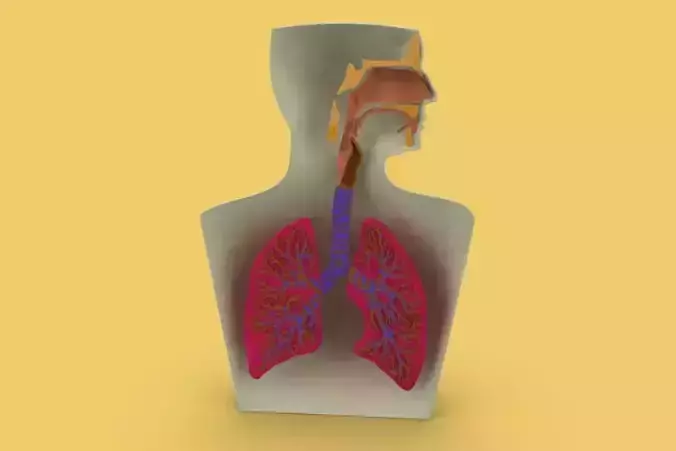

Sincerely Your, SURF3DMORE INFORMATION ABOUT 3D MODELS :LUNGS ARE THE PRIMARY ORGANS OF THE RESPIRATORY SYSTEM WHICH HELP IN THE EXCHANGE OF GASSES. THE OTHER MAIN PARTS OF THIS SYSTEM INCLUDE A SERIES OF AIRWAYS FOR AIR PASSAGES, BLOOD VESSELS AND THE MUSCLES THAT FACILITATE BREATHING.

THE LUNGS ARE THE PRIMARY ORGANS OF THE RESPIRATORY SYSTEM IN HUMANS AND MOST ANIMALS INCLUDING A FEW FISH, AND SOME SNAILS. IN MAMMALS AND MOST OTHER VERTEBRATES, TWO LUNGS ARE LOCATED NEAR THE BACKBONE ON EITHER SIDE OF THE HEART. THEIR FUNCTION IN THE RESPIRATORY SYSTEM IS TO EXTRACT OXYGEN FROM THE AIR AND TRANSFER IT INTO THE BLOODSTREAM, AND TO RELEASE CARBON DIOXIDE FROM THE BLOODSTREAM INTO THE ATMOSPHERE, IN A PROCESS OF GAS EXCHANGE. RESPIRATION IS DRIVEN BY DIFFERENT MUSCULAR SYSTEMS IN DIFFERENT SPECIES.

The lungs are a pair of spongy, air-filled organs located on either side of the chest (thorax). The trachea (windpipe) conducts inhaled air into the lungs through its tubular branches, called bronchi. The bronchi then divide into smaller and smaller branches (bronchioles), finally becoming microscopic.